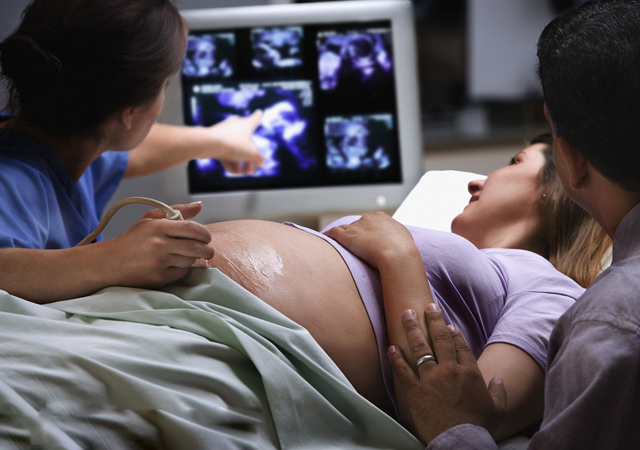

答:B超或者彩超有误。

如果仔细看的话,有些医院的彩超单下方会显示“结果仅供参考”等字样,其实这也是在说结果会有误差。所以,看宝宝的性别自然也会有误差。

误差的原因